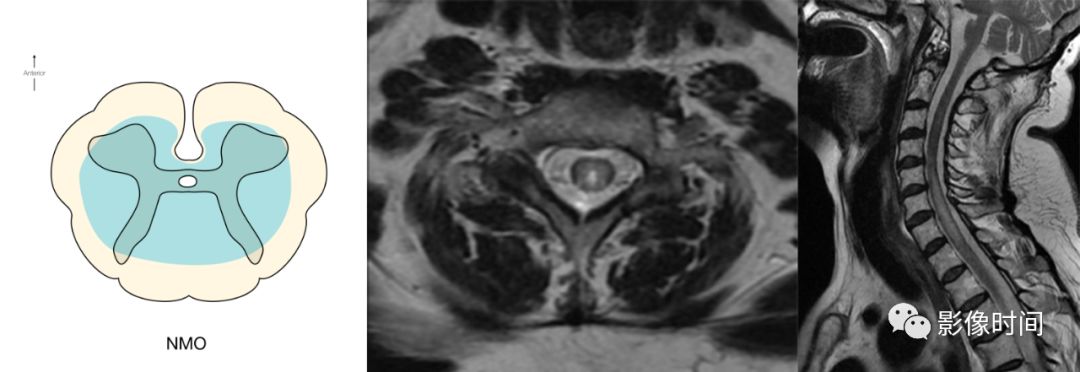

神经脊髓炎谱系疾病(neuromyelitis optica spectrum disorder,NMOSD):是一种由水通道蛋白-4(AQP-4)自身抗体介导的炎性脱髓鞘疾病,青年或中年女性较多见,临床常为双侧视神经炎和脊髓炎导致失明和截瘫,也可累及大脑。

MRI:

脊髓:病灶 T2WI 呈高信号,T1WI 呈稍低信号,急性期出现斑片状或云雾状强化,轴位常位于脊髓中央,长度>3 个椎体长度。亮点征:轴位 T2WI 很高信号的多发斑点,信号高于脑脊液,特异性=97%。

病灶分布于脊髓中央,长度大于3个椎体,亮点征

多发性硬化(Multiple sclerosis,MS)亦是一种严重的中枢神经系统自身免疫脱髓鞘病变,免疫球蛋白分泌 B 细胞和浆细胞的克隆性扩增,可使 CSF 中出现寡克隆带特征。

脊髓:颈髓较常受累,病灶 T2WI 呈高信号,T1WI 呈稍低信号,轴位常分布于前索、侧索或者后索,长轴 ≤ 2 个连续阶段椎体,急性期呈斑片状、结节状或环形强化。

病灶位于侧索、长度小于3个椎体节段